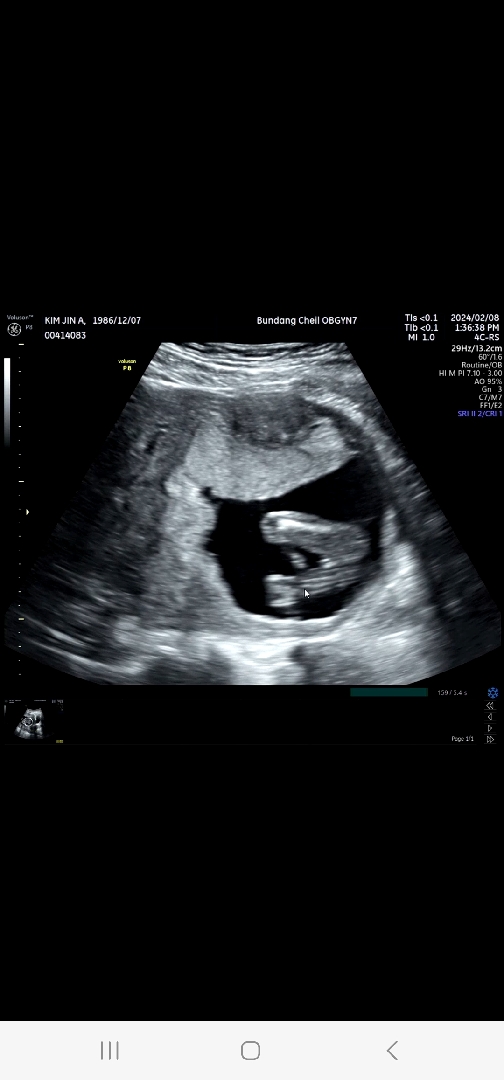

15주6일 딸이래요^^♡ 초음파사진 공유해요

작년에 12주차 유산하고 다시 온 아기라 입덧도 없고, 가슴은 커졌는데 배가 많이 나오지도않고 매번 아기가 잘 있는건지 걱정되요~ 12주.16주 생사확인 하는기분으로 병원갔는데 건강만해라 살아만 있어라 했는데 내심 바라던 딸이라니.. 기분 좋아 글 올려요^^ 다리사이에 뭐가 없다고~ 보자마자 딸이네요 해주셨어요!! 다들 새해 복 많이 받으세요^^